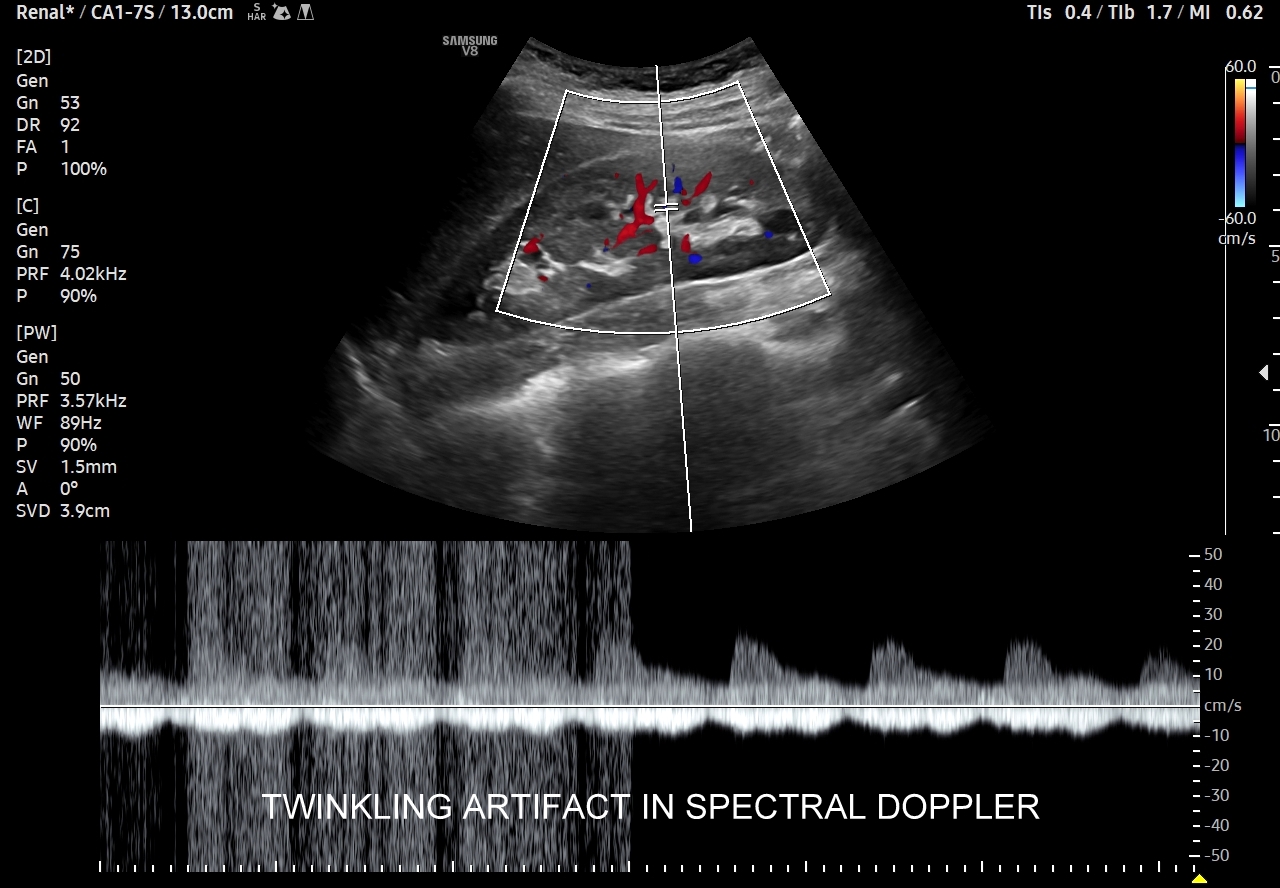

- Badanie USG Doppler przepływów nerkowych.

Multiparametryczne badanie USG (MPUS) jest rozwinięciem klasycznego USG jamy brzusznej zwykle w formie jednoczasowego zastosowania różnorodnych technologicznie trybów obrazowania USG, zarówno tzw. „nowych”, jak i „starych”. Wśród nowych najważniejszym jest obrazowanie mikrounaczynienia (MVI / MVF), a w dalszej kolejności tryby elastograficzne oraz metody ilościowej oceny stłuszczenia wątroby. Wymienione „nowe” modalności w połączeniu ze „starymi”, przede wszystkim z Dopplerem spektralnym i color-Dopplerem, stanowią rdzeń nowoczesnej ultrasonografii MPUS, gdyż umożliwiają pozyskanie znacznie większej ilości informacji z badania USG w porównywalnym przedziale czasowym, a przez to uzyskanie jego większej wartości diagnostycznej. Przykładowo badanie MPUS umożliwia różnicowanie pseudoguzów od guzów prawdziwych, ocenę żywotności tkanek, biologii nowotworów, funkcjonalną ocenę nerek i wątroby, poprawia obrazowanie dużych naczyń krwionośnych oraz charakterystykę podejrzanych torbieli.